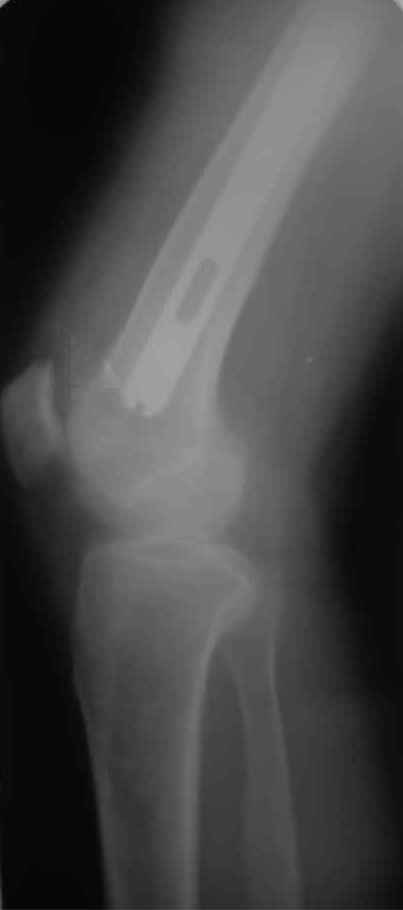

А нельзя ли увидеть и профиль бедра на всем протяжении, т.е. и весь протез, и весь стержень? И фас бы с коленом.

igor 20 Ноябрь 2009, 08:08

новые снимки